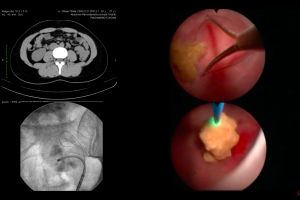

AMBULATORII EXTINSE LA JUDEȚEAN ȘI PEDIATRIE

Ambulatoriile de specialitate ale Spitalelor Judeţean de Urgenţă şi cel de Pediatrie din Piteşti vor fi extinse cu bani europeni, a anunţat azi conducerea Consiliului Judeţean. Astfel, la Spitalul Judeţean va fi construită o nouă clădire care va avea subsol, demisol, parter şi etaj, dar şi un...